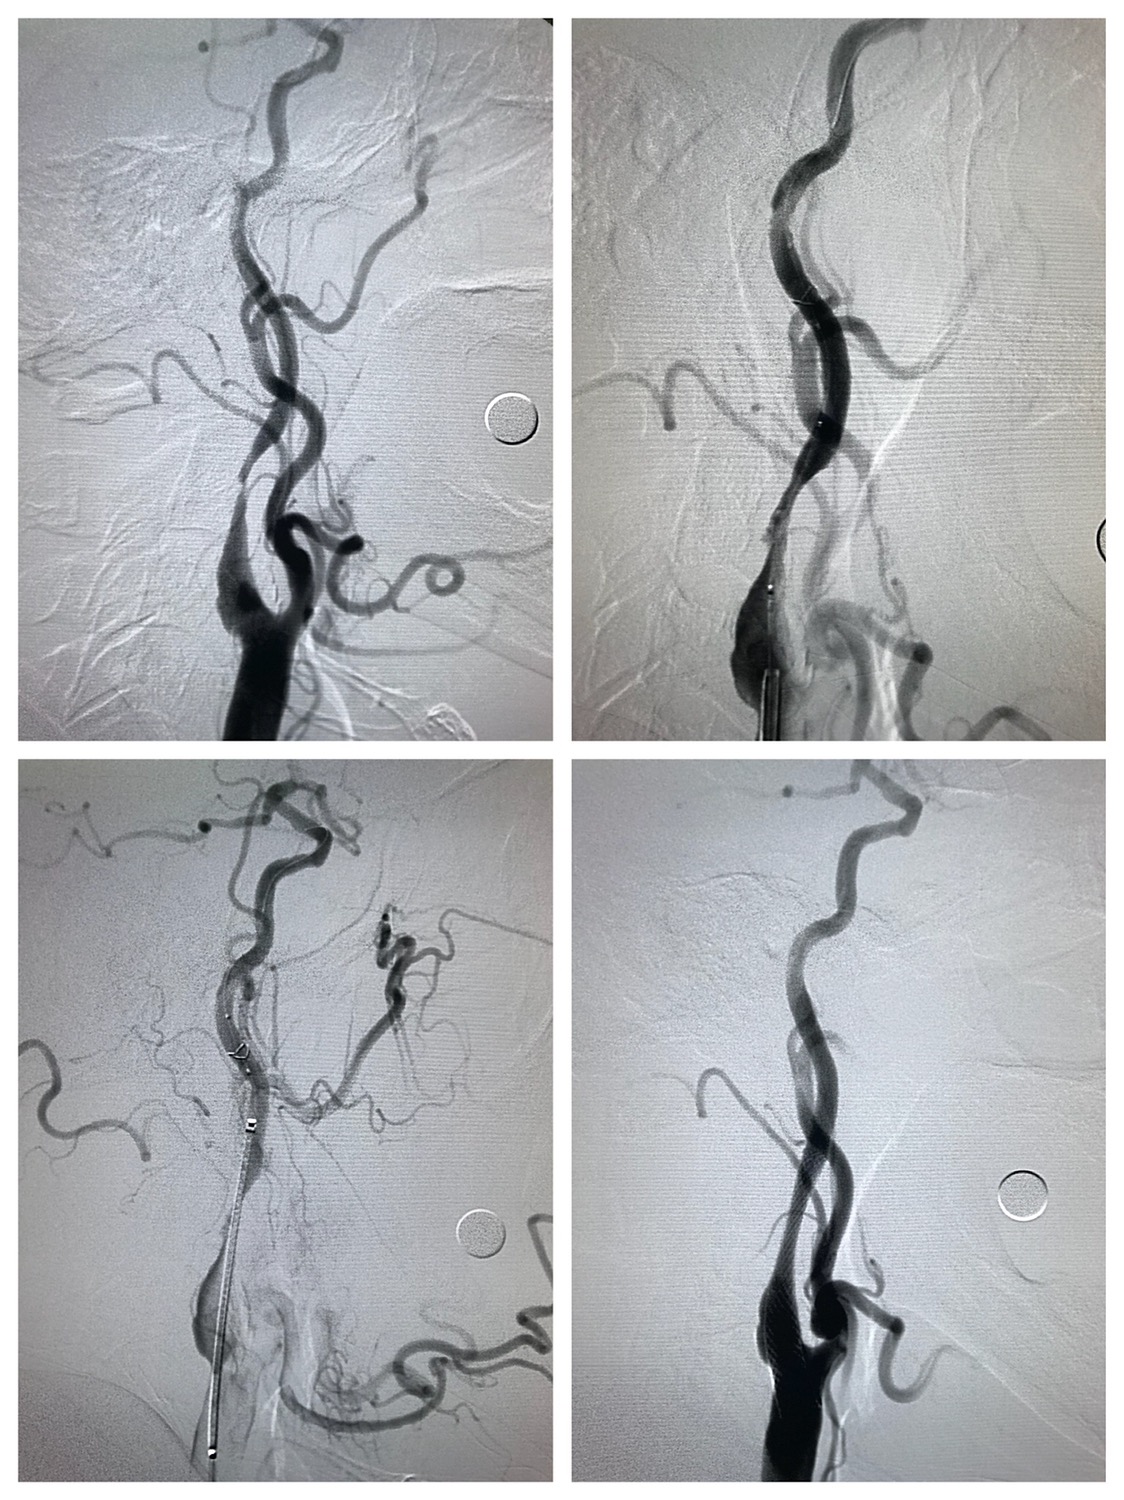

远端保护伞保护下,4/30球囊预扩后狭窄改善

WALLSTENT 9/40支架定位准确后释放

支架释放后狭窄解除

支架完全覆盖斑块,狭窄解除,支架形态柔顺贴合血管,无明显残余狭窄

术后颅内血供明显改善,胚胎型大脑后动脉显影良好。